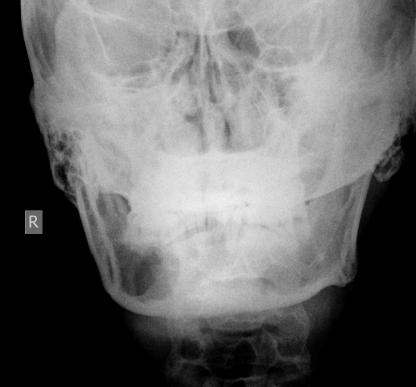

以下是引用吴教授在2010-6-20 14:53:00的发言:[br]右侧下颌骨见单房状较大囊状透光区,期内未见未见间隔,牙根部分吸收及受压移位,我考虑;2造釉细胞瘤可能性大。2不除外颌骨囊肿。

以下是引用拾荒者在2010-6-20 20:44:00的发言:[br]下颌囊状透亮影透光度较好,密度均匀,无分隔,囊壁光滑完整,无分叶及切迹,囊内有正常牙根及牙根吸收表现,首先考虑巨大根尖囊肿;应该与单房型造釉细胞瘤及单房型巨细胞瘤鉴别。